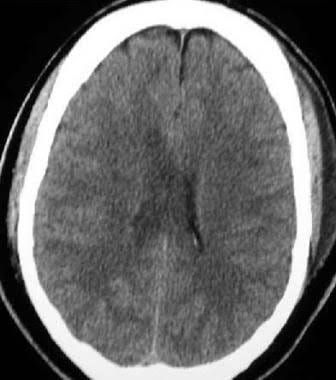

Diffuse axonal injury symptoms

The most common etiology of diffuse axonal injury involves high-speed motor vehicle accidents. The most common mechanism involves an accelerating and decelerating motion that leads to shearing forces to the white matter tracts of the brain.